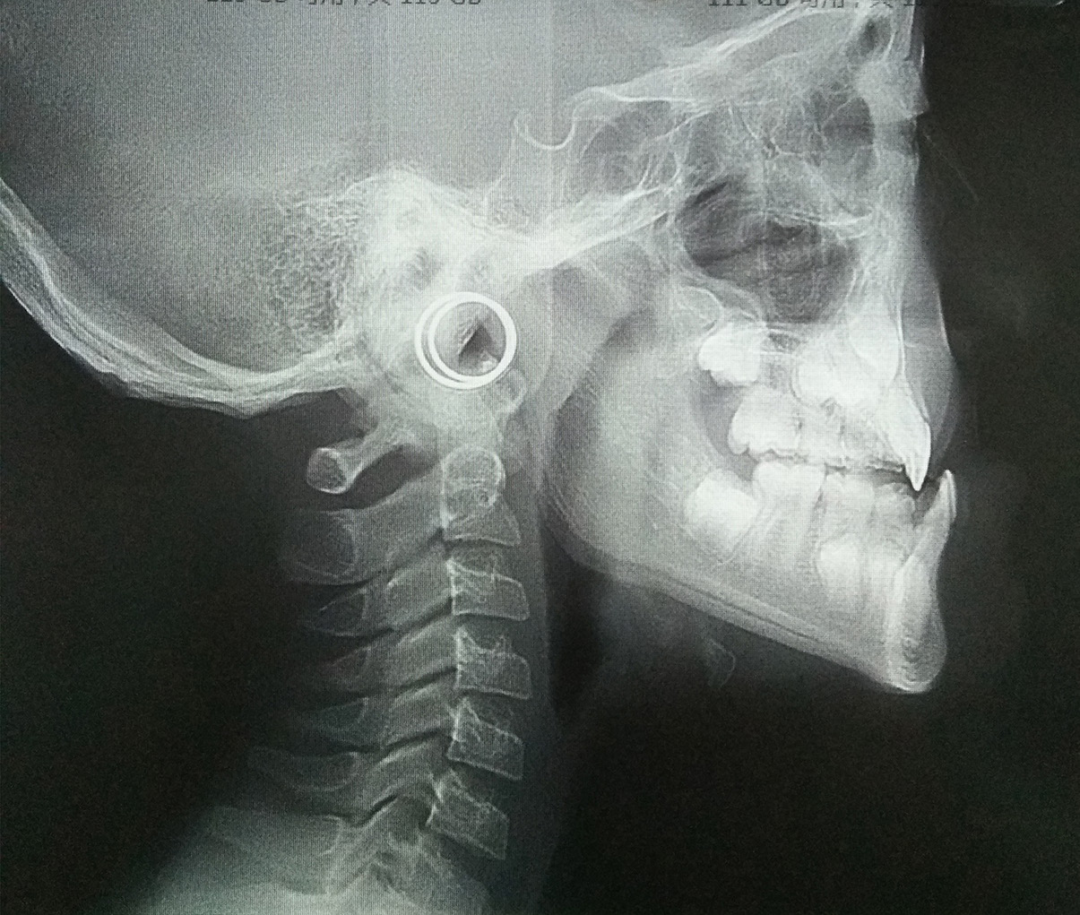

比如说这个孩子初诊时为替牙期,前牙对刃,但是患者家长拒绝接受矫正干预,一年半后复诊,前牙反颌重,并出现下颌前突。

头影测量中有一个方法简单有效——从 N 点(鼻根点)做眶耳平面的垂线,即 Mcnamara 线,上颌骨 A 点(上齿槽座点)距离该垂线的正常距离,0mm(儿童),1~2mm(成人);下颌骨 Pog 点(颏前点)距离该垂线的正常距离,- 6mm(儿童),- 2mm(成人)。

上颌后缩情况

下颌前突情况